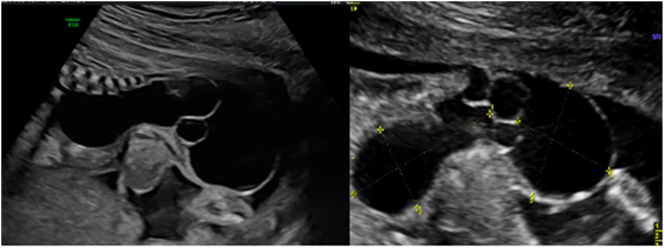

Case presentation: This is a unique case of a 29-year-old second gravida, suspected of having a fetal sacrococcygeal dysplasia differentiable between Type 2 SCT and terminal myelocystocele. An MRI revealed no typical SCT changes, as a matter of course, the diagnosis of myelocystocele could not have been excluded. The results of the genetic examination allowed to exclude the chromosomal pathology. Punctuation of the external component of the formation and a cytological examination were suggested. Nevertheless, the patient and her partner refused further studies and insisted on the termination of pregnancy. Medical abortion was induced and histological findings confirmed fetal morphology to be mature SCT.